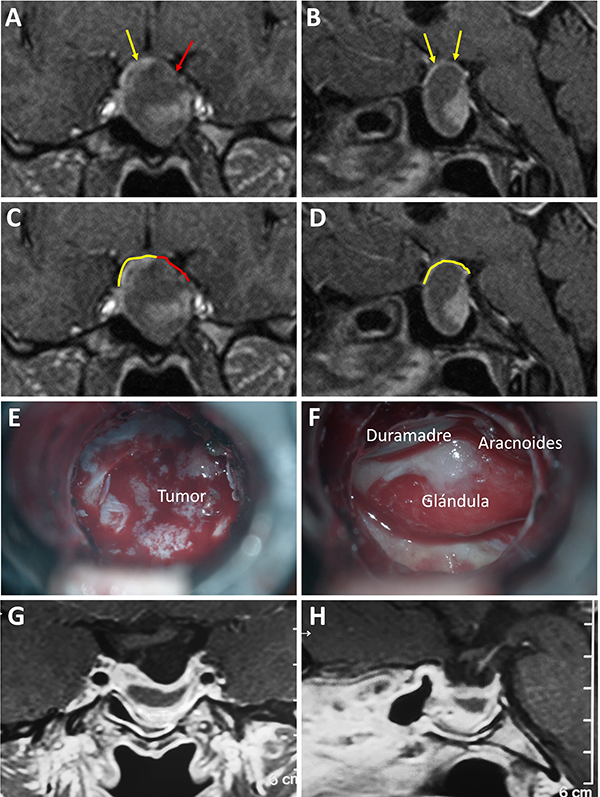

Una clasificación clásica de los adenomas es según su tamaño. Se los clasifica en microadenoma <10 mm (fig. 2), macroadenoma >10 mm (fig. 3), y adenoma gigante > 30 mm (fig. 4). Esta clasificación es importante ya que los índices de remisión están ligados al tamaño del adenoma y también su recidiva.12

Figura 3: Macroadenoma. A-B: RM preoperatoria; C-D: Campo visual preoperatorio; E-F: RM postoperatoria; G-H: Campo visual postoperatorio.

El techo de la fosa pituitaria está constituido en condiciones normales por un máximo de 2 estructuras: duramadre (diafragma selar) y aracnoides.65,66 En condiciones patológicas, cuando existe un adenoma hipofisario, éste empuja hacia arriba a la glándula. De este modo, la interfase entre el tumor y el LCR se encuentra constituida por un máximo de 3 elementos: glándula, duramadre y aracnoides. Cabe destacar que la aracnoides es el único elemento constante. A los elementos que constituyen esta interfase el equipo de Tucumán los denominó “barrera selar”.11,60

Existen 3 subtipos de barrera selar según los hallazgos intraoperatorios, luego de resecar el tumor:

Un factor interesante de este novedoso concepto es que el tipo de barrera puede evidenciarse en la RM preoperatoria. De este modo, existen 3 subtipos de barrera selar según la radiología:

Los pacientes con una barrera débil tienen mayor riesgo de fístula intraoperatoria de LCR. La barrera fuerte es un factor protector de fístula de LCR.11,60

Figura 7: Barrera selar mixta. A y C) RM preoperatoria corte coronal; B y D) RM preoperatoria corte sagital; E-F) Hallazgos intraoperatorios; G-H) RM postoperatoria. Flechas y líneas: color rojo indican barrera débil; color amarillo indican barrera fuerte. Tomado deVillalonga JF, Ries-Centeno T, Sáenz A, Solari D, Cervio A, Campero A. The mixed sellar barrier: a new subtype of this novel concept. World Neurosurg. 2019;132:5-13.